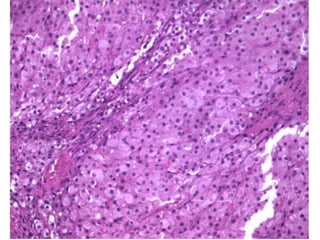

Cervical metaplasia

Uterine cervix = Cervix uteri 2.

• tunica mucosa exocervicalis (vaginal surface od

cervix)

– non-keratinized stratified squamous epithelium (similar to

vaginal epithelium)

– transition in area of ostium uteri (external orifice of uterus)

– borderline with columnar epithelium lies in endocervix – is

not visible

• ectropium = endocervical epithelium extends to the

vagina (after labour)

• ectopia = epithelial metaplasia= precancerosis

(columnar epithelium is replaced by stratified

squamous – transformation zone) → conization

• HPV